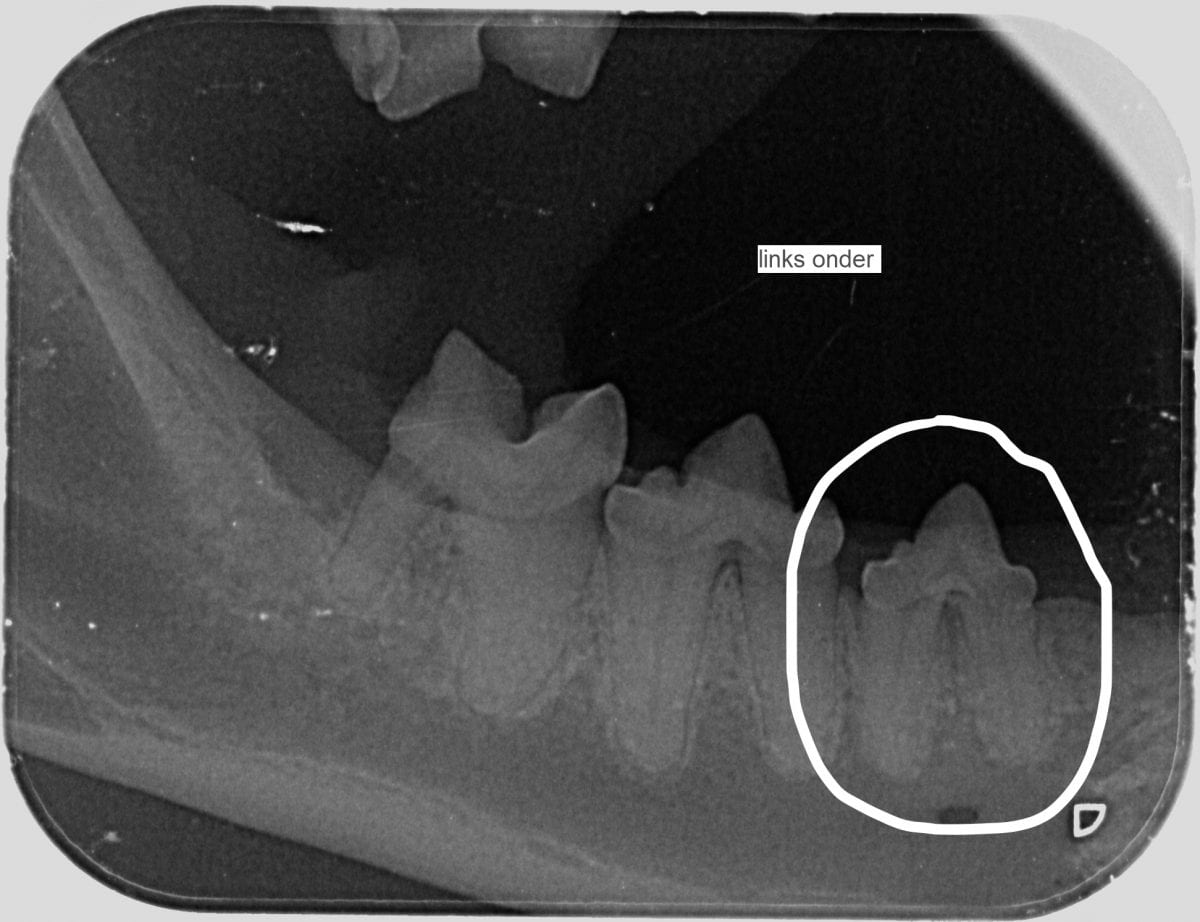

Onderaan deze pagina staan 2 dentale röntgenfoto’s. Op de eerste foto hieronder zie je een kies die al bijna helemaal opgelost is. De foto ernaast laat een kies zien waarbij de wortels nog aanwezig zijn.